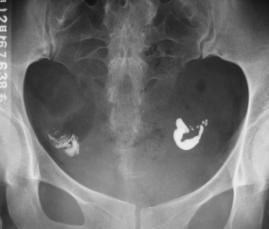

異位妊娠是婦科常見急腹症,近年來發病率明顯增加,而且未育患者增多。隨著快速、敏感的β-hCG檢測技術的開展,高解析度的B超套用,使大部分異位妊娠在未破裂前得以診斷,為藥物保守治療提供了條件[1],對仍需保留生育功能的患者,選擇何種藥物及最佳治療方案是一個值得探討的問題。藥物保守治療異位妊娠取得了很大進展,已經成為主要的治療手段[2],其優點是它既能殺死胚胎組織,又不破壞輸卵管組織,從而保持輸卵管通暢。目前,國內外關於異位妊娠保守性藥物治療的報導多數選用氨甲喋呤(MTX)[3,4]。

輸卵管但氨甲喋呤的化療反應對機體損害大,副作用多。米非司酮問世以來,逐漸被套用於治療異位妊娠,對停經天數少、體內孕激素水平相對較低者,米非司酮抗早孕效果更好。本文對50例異位妊娠患者,以氨甲蝶呤(methotrexate,MTX)為對照,觀察米非司酮(mifepristone,Mif)治療異位妊娠的療效,來探討一種安全、有效、套用方便、副作用少的治療方法。

研究對象及分組,1999年5月~2003年10月異位妊娠入院確診患者50例,年齡最小20歲,最大41歲,平均27歲,停經時間38~65天。診斷依據病史、婦科檢查、血β-hCG及B超檢查,經診刮除外子宮內妊娠。服藥對象:(1)異位妊娠未破裂型或輸卵管妊娠破裂,但出血少;(2)B超檢查輸卵管妊娠包塊直徑6000U/L而患者有藥物保守治療的要求,無米非司酮禁忌證者。(6)肝、腎功能均正常,外周血WBC、RBC、PLT均在正常範圍。